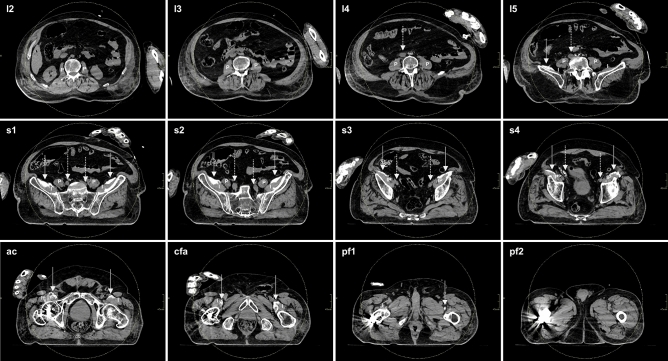

Figure 3.

Axial CT slices detailing typical spread of injectate after (bilateral) S-FICB-H. The LA-based contrast mixture was determined to reach a maximum height corresponding to the fifth lumbar vertebra on the left side and the intervertebral disc of lumbar vertebrae four-five on the right side. Medial spread of contrast stayed anterior to the iliopsoas muscles and iliac arteries. As such, contrast remained removed of the location of the lumbar plexus and ON, both in the cranial and medial directions. Dotted arrows point to the iliac arteries, solid arrows point to the contrast. l lumbar vertebra, s sacral vertebra, ac acetabulum, cfa common femoral artery, pf proximal femur, P psoas muscle, I iliacus muscle, IP iliopsoas muscle.

Spread of the injectate towards the lumbar plexus was measured in relation to the femoral head. Truncal spread was found in only two of nine (22%) I-FICBs and as such, I-FICB was excluded from statistical analysis. The mean cranial spread of S-FICB-H (14.00 ± 3.16 cm) was significantly more than that of S-FICB (10.28 ± 2.95 cm, p = 0.046), or FNB (5.30 ± 2.86 cm, p ≤ 0.001). Injectate reached higher for S-FICB than for FNB (p = 0.008). Similar distribution patterns were observed when cranial injectate spread was related to the vertebral column, as shown in Table 2, and demonstrated for S-FICB-H in Fig. 3.